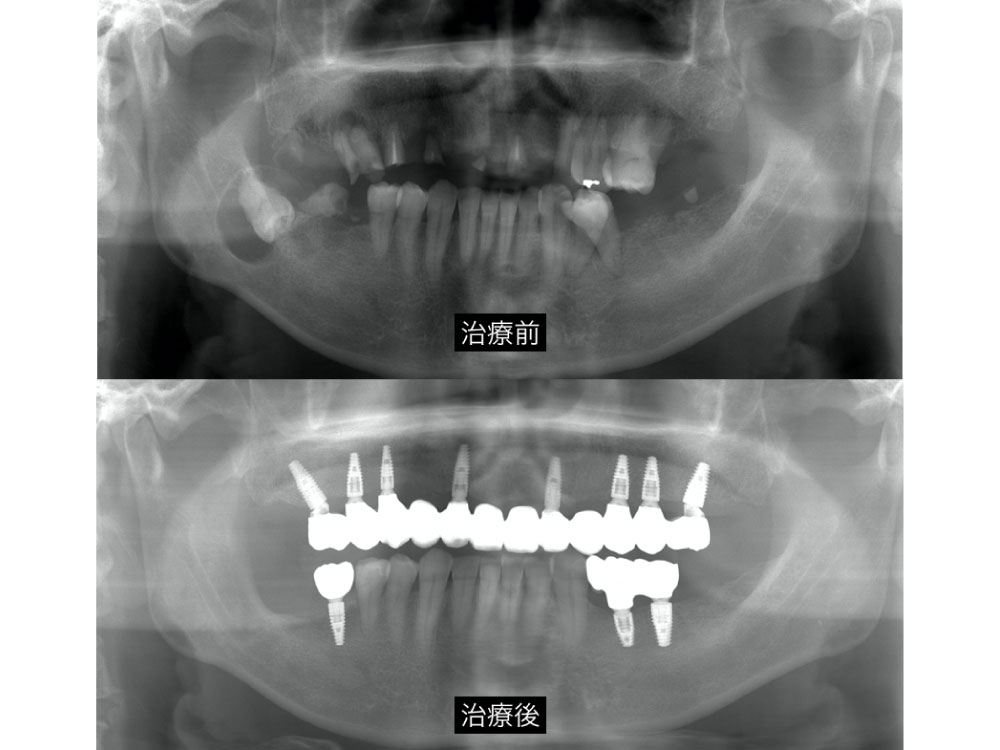

不幸にして多くの歯を失ってしまった方の再構築の症例

一度崩壊してしまった歯を再建するのは容易ではありませんが、諦めなければ少しでも明るい未来はあります。

| 治療期間 | 1年6ヶ月 |

| リスク | 一時的にしみるなどの痛みを伴う事があります。 |

| 治療費用 | インプラント¥400,000〜(税別) セラミック¥60,000〜160,000(税別) |